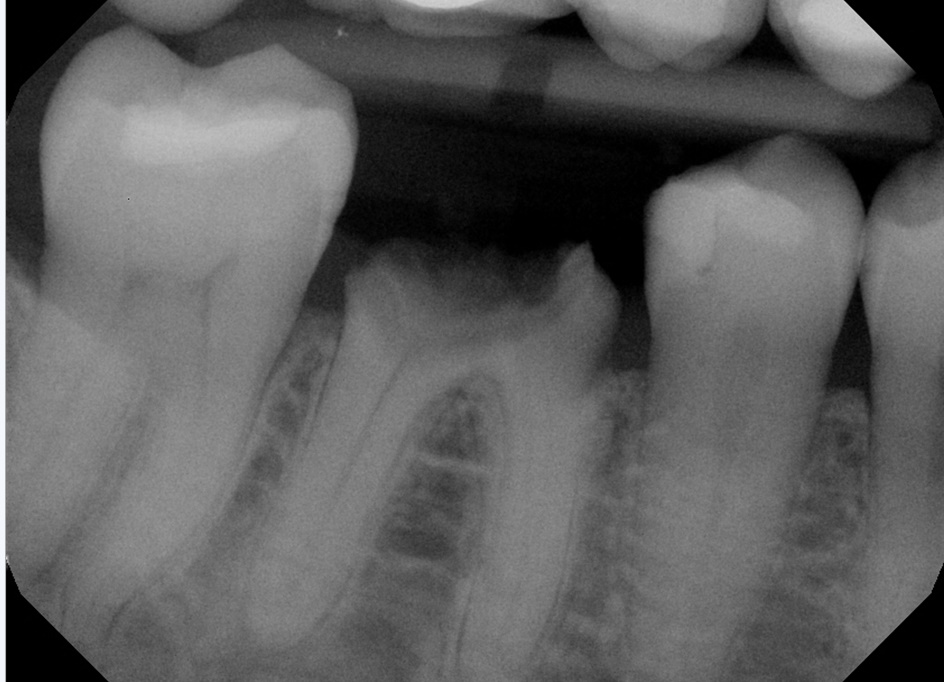

Septum implant loading using DSI Top Drill kit case